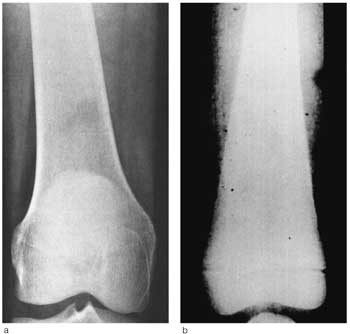

I tillegg til beinmargsaffeksjon er skjelettplager vanlig. En rekke beinsykdommer er assosiert med Gauchers sykdom, blant annet osteoporose, avaskulær nekrose (f.eks. Calvé-Legg-Perthes sykdom) og destruksjon av leddflater (9, 10). Radiologisk regnes deformiteter av lårbeina (erlenmeyerkolbedeformitet) som karakteristisk for Gauchers sykdom (fig 2), noe begge våre pasienter fremviste. Denne deformiteten skyldes nedsatt evne til remodellering av knoklene. Ubehandlet kan skjelettforandringene bli så uttalte at de medfører spontanfrakturer og alvorlig invaliditet.